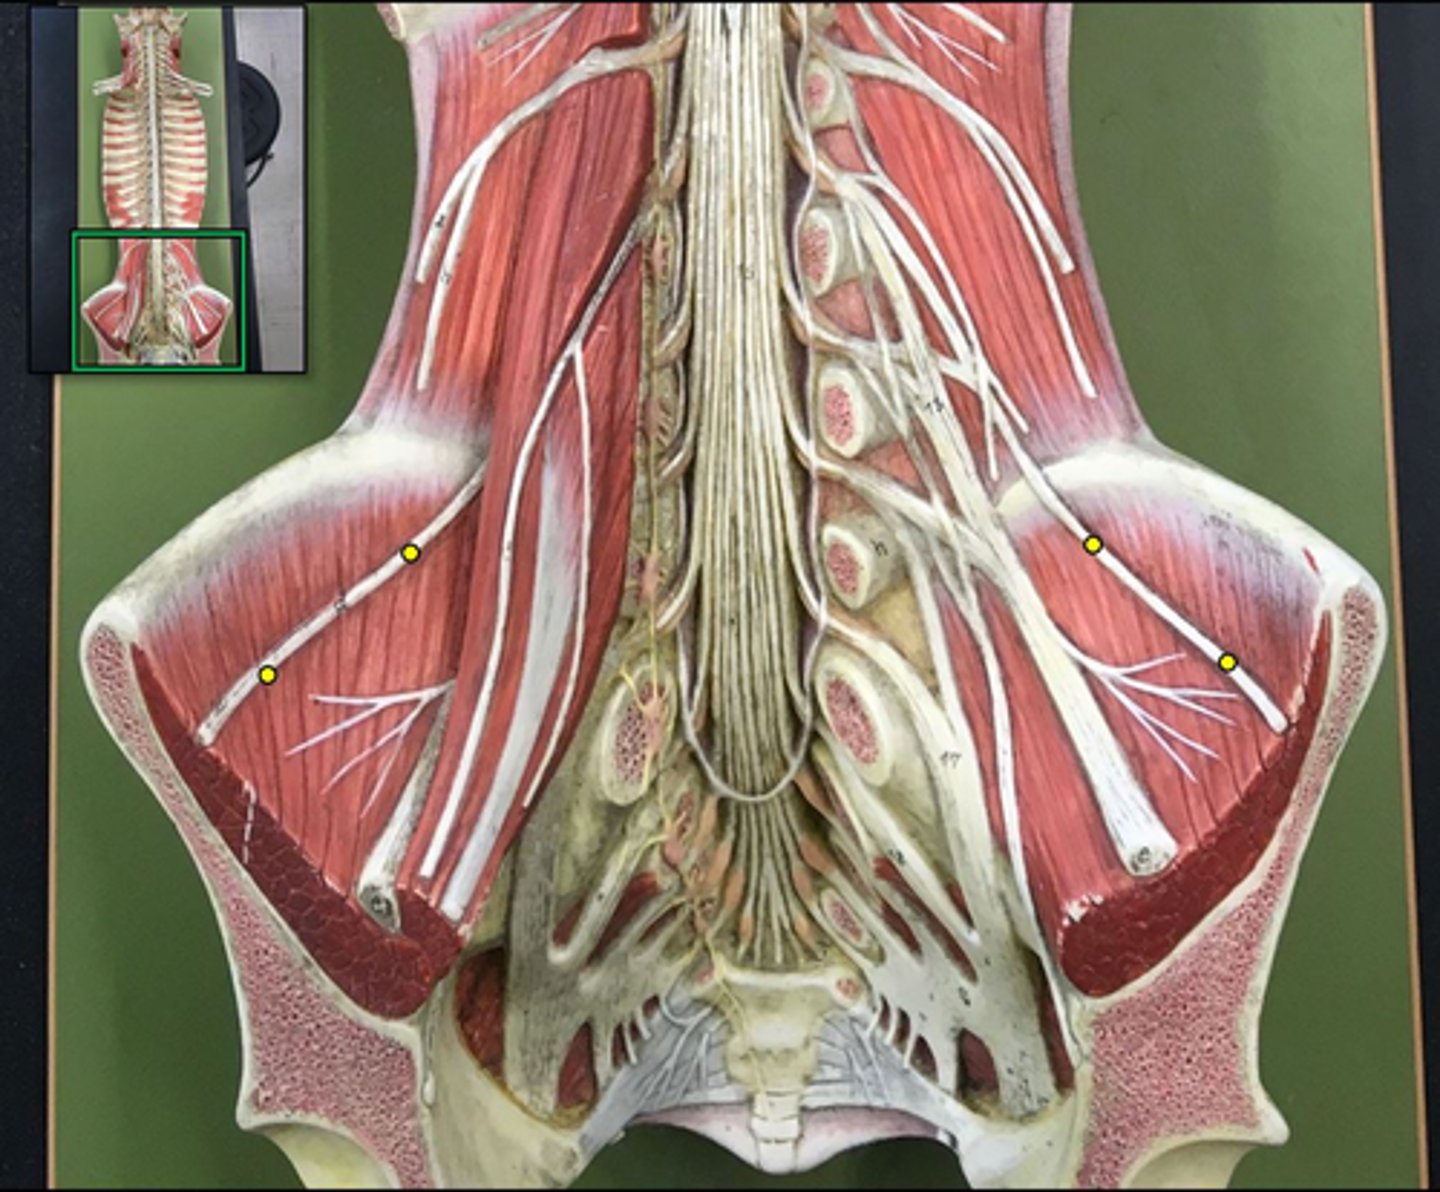

posterior root

axons of sensory neurons

posterior root ganglion

anterior root

axons of motor neurons

spinal nerve

cauda equina

bundle

lumbar plexus

T12- L4

sacral plexus

L4- S4